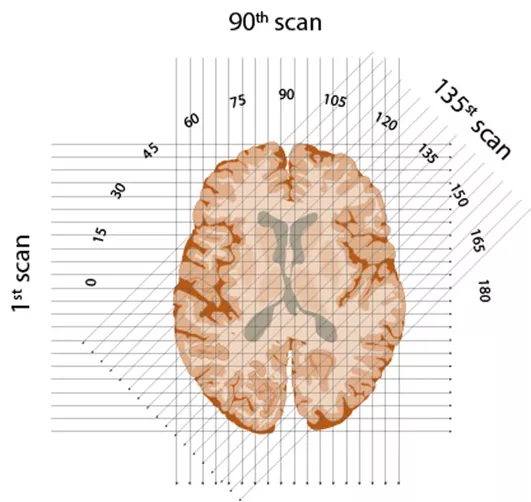

x射線以半圓形從1到180度的角度照射到大腦的各個“切片”。Edmund S. Higgins, CC BY-ND

首先,他在概念上像切片面包一樣將大腦分成連續的切片。然後,他計劃用一系列的x射線穿過每一層,對半圓中的每一度重複這一步驟,在大腦的另一側捕捉每束光線的強度——穿過密度較低材料的光線較強。

計算每一束穿過物體的x射線強度,然後用一種不可思議的算法進行逆向運算,這樣就有可能構造出一幅圖像。Edmund S. Higgins, CC BY-ND

最後,在亨斯菲爾德最具獨創性的發明中,有一種可以基於所有切片重建大腦圖像的算法。利用當時最快的新計算機之一進行逆向計算,他可以分析出每層大腦切片的每個小方塊的值。成了!